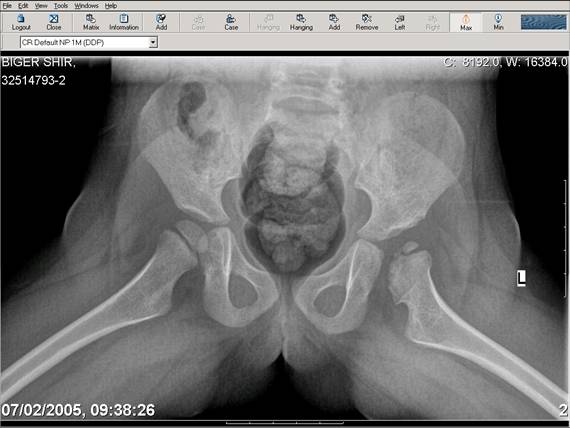

Здравствуйте, уважаемые коллеги.Обратилась девочка 6-ти лет из жалобами на боль в левом т/б суставе,хромоту Из анамнеза : ребенок лечился с рождения по поводу врожденного вывиха бедер. В возрасте 3- х лет в одной из клиник была выполнена остеотомия таза по Пембертону и варизирующая остеотомия бедра слева, справа - остеотомия таза по Солтеру и остеотомия бедра. Посоветуйте тактику лечения. С уважением Ihor

Smotritsya parshivo konechno(pseudoacetabulum,partial AVN), no v6 let ya by popytalsya ispravit chto moghno:shortening (ne boyatsya ubrat bolshoi fragment),derotation(30 gradusov ne bolshe)+pelvic osteotomy in true acetabuluam area.Obyazatelno takghe open reduction with wide capsular exposure.

Уважаемой Ihor! Следует дообследовать ребенка, проведя РКТ или МРТ. Необходимо установить взаимоотношение головки бедренной кости и вертлужной впадины слева, оценить угол антеторсии и истинный ШДУ. Далее решать вопрос об оперативном лечении. Скорее всего показана деторсионно-варизирующая остеотомия в межвертельной области левого бедра и остеотомия таза типа Солтера (хотя ацетабулярный индекс великоват, т.е. более 30-35 градусов). Справа следует понаблюдать и периодически проводить курсы ФТО и ЛФК. Если Вы не имеете опыта реконструктивной хирургии ТБС у детей, то лучше отправить пациента к детским ортопедам. АИФ